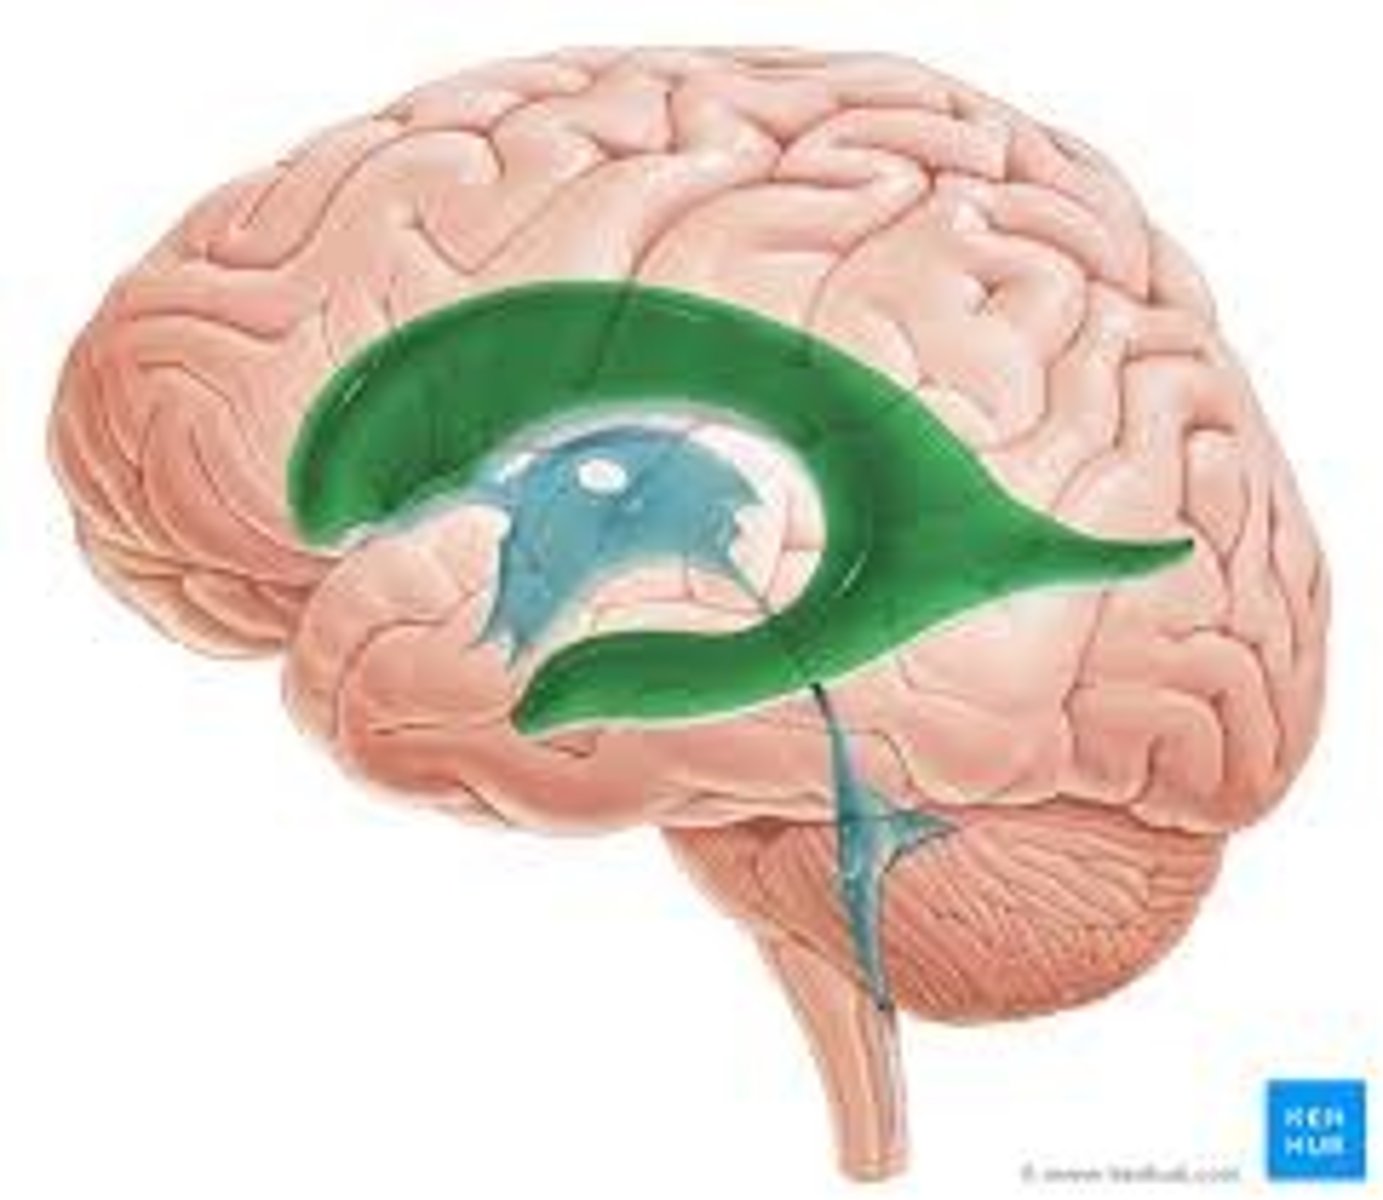

right and left lateral ventricles

third ventricle

fourth ventricle

cerebral aqueduct (mesencephalic aqueduct)

interventricular foramen